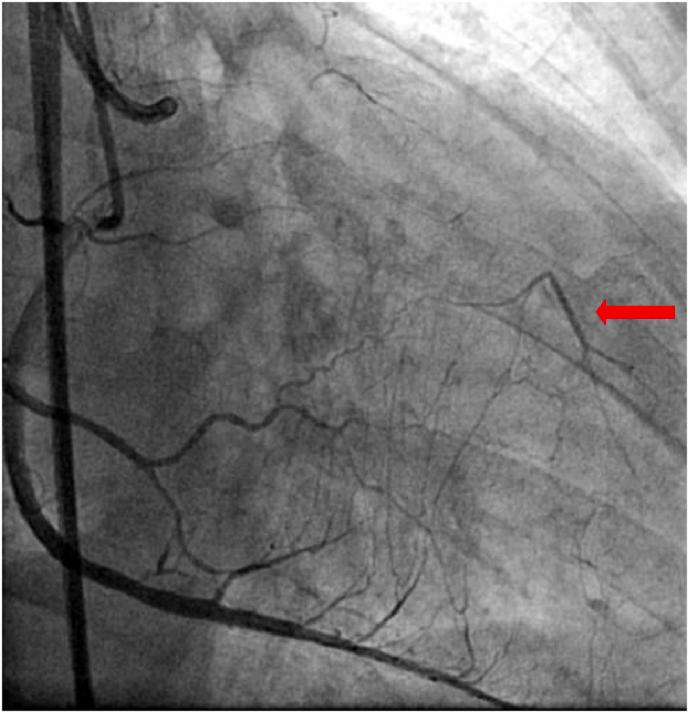

To investigate the disparities in coronary collateral circulation (CCC) and peripheral serum metabolites among patients presenting with chronic total occlusion (CTO) of the coronary arteries, a non-targeted metabolic approach was employed.

A cohort of 22 patients diagnosed with CTO of coronary arteries in the context of coronary heart disease (CHD) was selected for blood sample collection from CCC and peripheral arteries. The patients were categorized into two groups, namely CTO-C and CTO-P. The Waters UPLC I-Class Plus is combined with the Q Exactive high-resolution mass spectrometer for metabolite separation and detection. The acquired raw data from mass spectrometry is subsequently imported into Compound Discoverer 3.2 software for comprehensive analysis, which seamlessly integrates the BGI Metabolome Database (BMDB), mzCloud database, and ChemSpider online database. Subsequently, the identified differential metabolites were subjected to a metabolic pathway enrichment analysis, as documented in the Kyoto Encyclopedia of Genes and Genomes (KEGG) database.

A total of 403 differential metabolites were identified in CCC and peripheral serum samples from patients with CTO of coronary arteries in CHD. Compared to the CTO-P group, the CTO-C group exhibited decreased levels of metabolites such as Testosterone, dehydroepiandrosterone (DHA), deoxyacetone, while demonstrating increased levels of metabolites including Progesterone, androstanone, l-threonine. The biosynthesis pathway of steroid hormones emerges as the key metabolic pathway significantly associated with differential metabolites.

Through metabolomics analysis, distinct differences in the CCC and peripheral serum metabolites have been identified among patients with CTO of coronary artery. Notably, a significant association between the steroid hormone biosynthesis pathway and CCC has been observed.